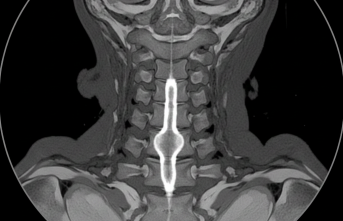

Omuriliğin Sessiz Misafiri: Siringomiyeli